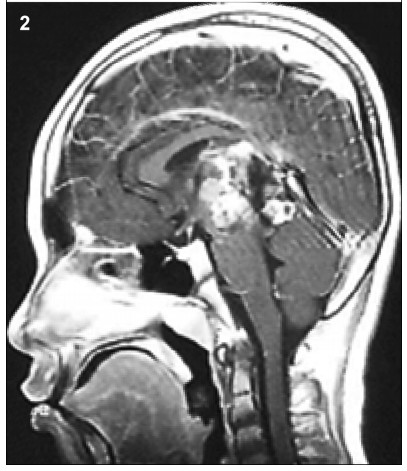

1 Case presentation 1.1 History A space-occupied cystic lesion in the rear of the third ventricle was detected in an 8-year-old boy presenting with symptoms of raised intracranial pressure (ICP) and a diagnosis of “cystic lesion” 3 years ago (Figure 1). He underwent a ventricle-peritoneal shunt operation without serum tumor marker test and became asymptomatic soon after the operation. Intermittent regular brain Magnetic Resonance Imaging (MRI) demonstrated no evidence of massive aggrandizement during the following 2 years. Then, 2 months ago,he rapidly developed unsteady gait and confined ocular motor function,followed by acute aggravating clinical symptoms. MRI scans showed that the mass had remarkably enlarged in size and the solid component had become predominant,instead of the prior cystic lesion. Furthermore,the transitional parenchyma tumor was heterogeneously and notably enhanced in contrast-enhanced MR image (Figure 2).

Figure 1 The MRI (2013) showed a cystic lesion in the rear of third ventricle.

Figure 2 The MRI (2015) showed the mass remarkably enlarged in size and the solid component became predominant instead of prior cystic lesion.